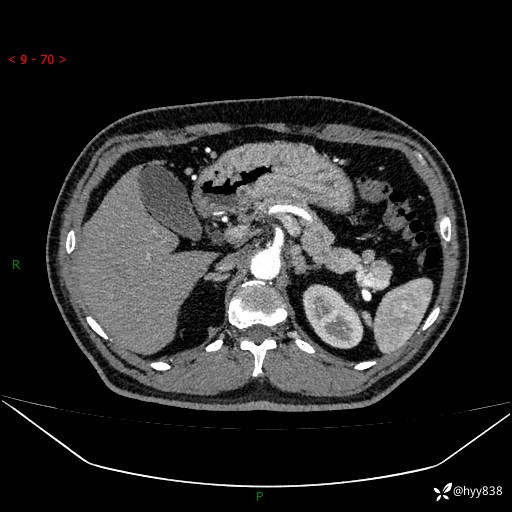

增强动脉期